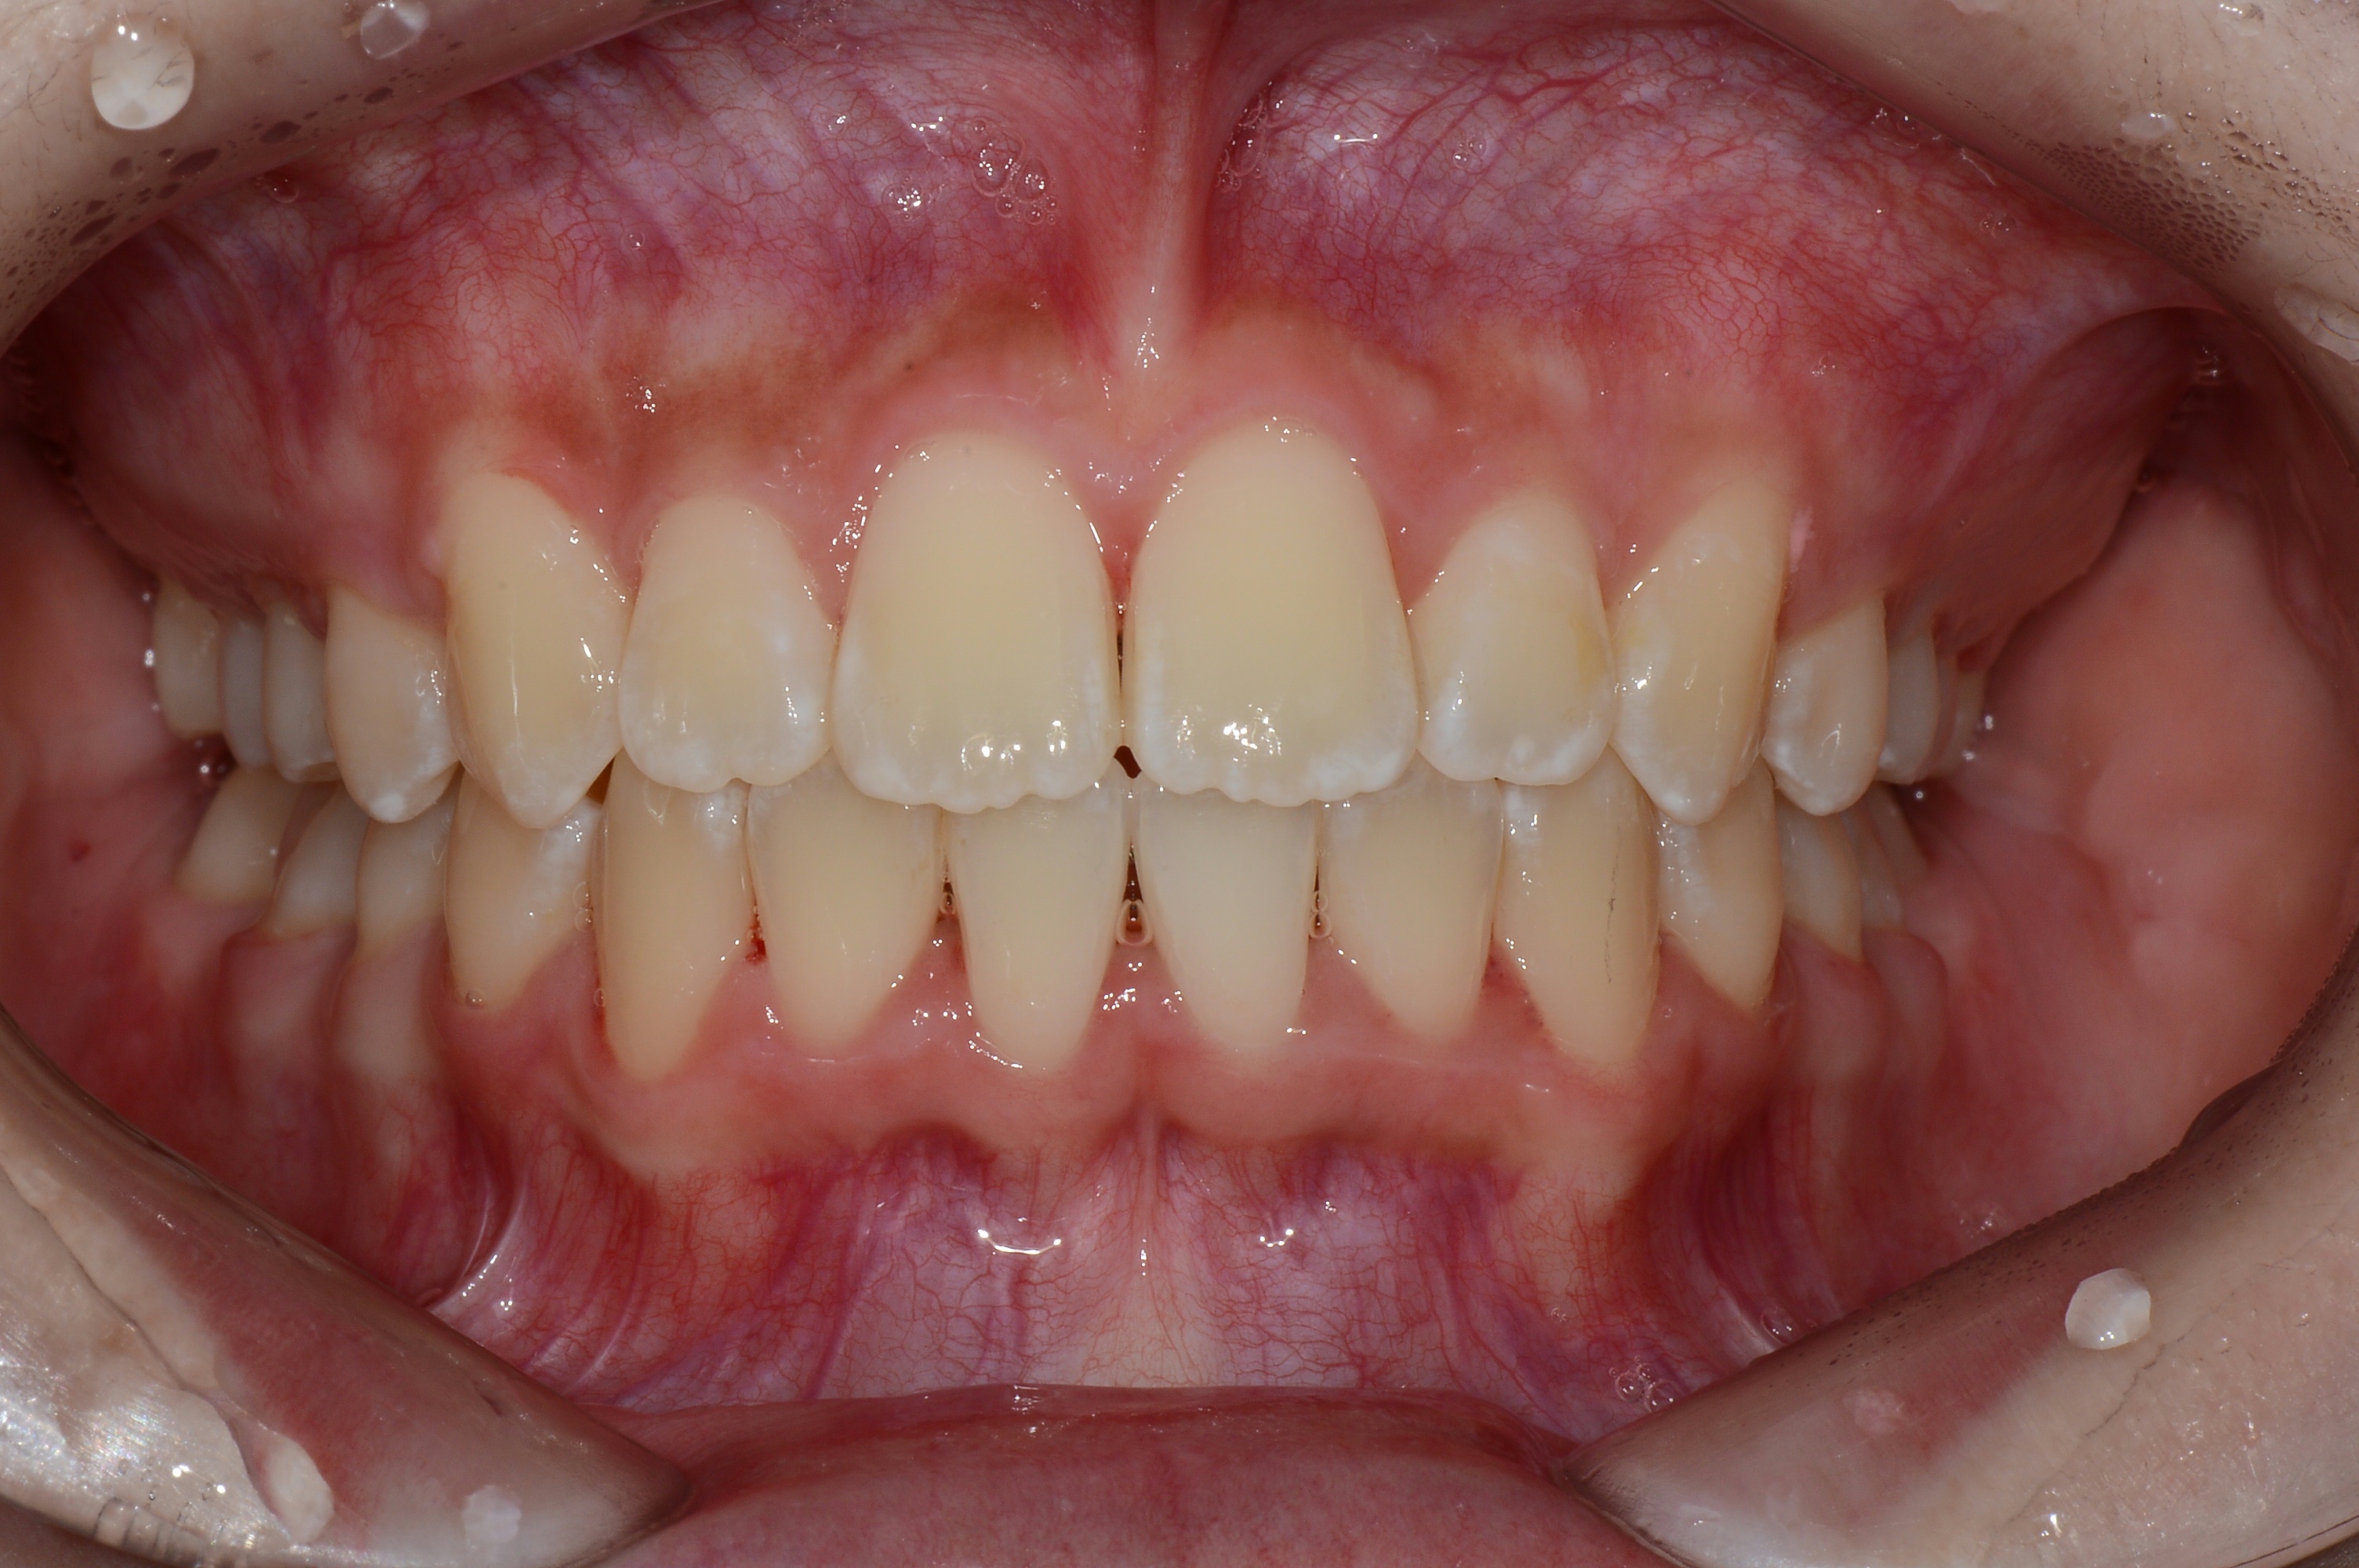

치료 후 사진입니다.